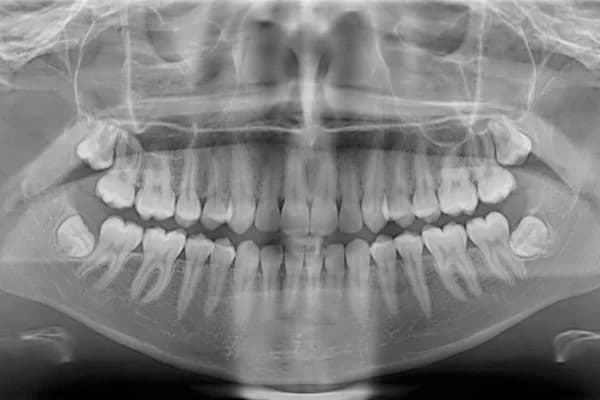

Radiología: Placas Panorámicas

Ofrecemos radiografías panorámicas de alta resolución que nos permiten tener una visión clara y detallada de toda tu boca para brindarte así, un diagnostico preciso.

Estas imágenes nos ayudan a identificar problemas ocultos, planificar tratamientos complejos y asegurarnos de que cada paso que demos esté basado en información precisa.

Panorámicas

Una sola toma de toda la boca con equipo especial; útil para planificar, no para detectar caries incipientes.